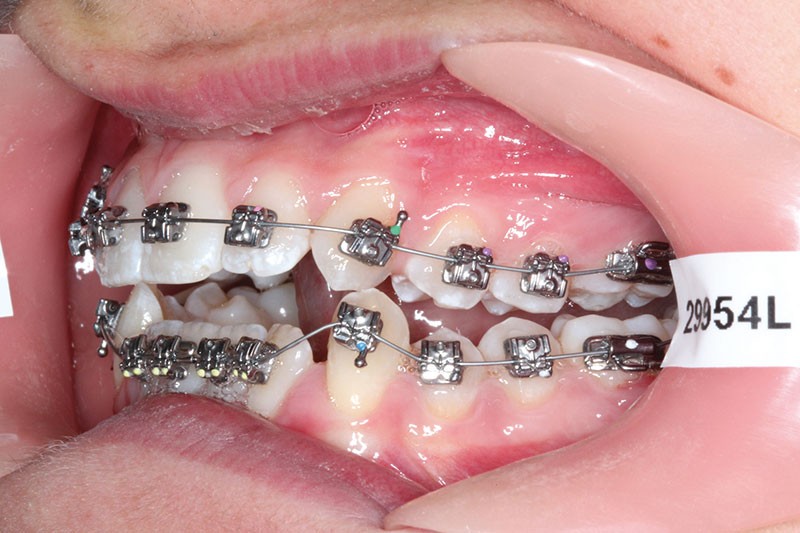

1re phase : recul des secteurs latéraux mandibulaires avec le Motion Classe III Carriere (fig. 4 à 6)

Nous mettons en place des bras latéraux Motion associés à des élastiques intermaxillaires ancrés sur des brackets sur 17 et 27 et une gouttière thermoformée maxillaire portée jour et nuit :

• 1er mois : élastiques 6 oz. 1/4”

• 2e mois et suivants : élastiques 6 oz.1/4“

L’objectif de cette étape est d’obtenir un recul des secteurs latéraux mandibulaires afin de positionner les molaires et canines en classe I et de réorienter le plan d’occlusion en haut en avant.